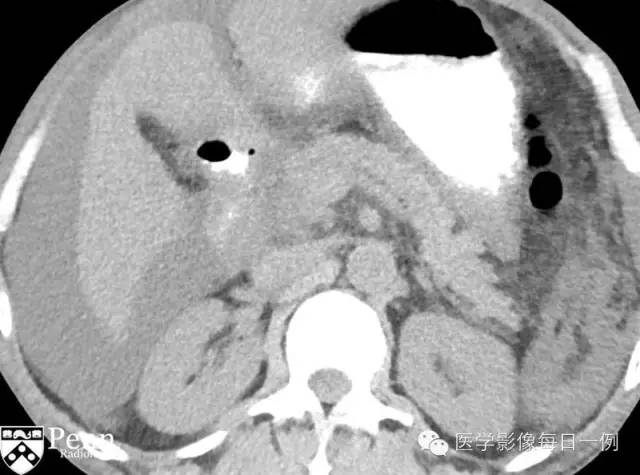

Contrast-enhanced CT images

CT: 胰头增大,沟部可见低密度、轻度强化肿块。

图1平扫示胰头肿胀,低密度肿块(黑箭),十二指肠壁增厚并管腔狭窄(白箭)。

增强扫描动脉期示胰头肿胀,低密度肿块(黑箭),十二指肠壁增厚并管腔狭窄(白箭)。

增强扫描门脉期示胰头肿胀,低密度肿块(黑箭),十二指肠壁增厚并管腔狭窄(白箭)。